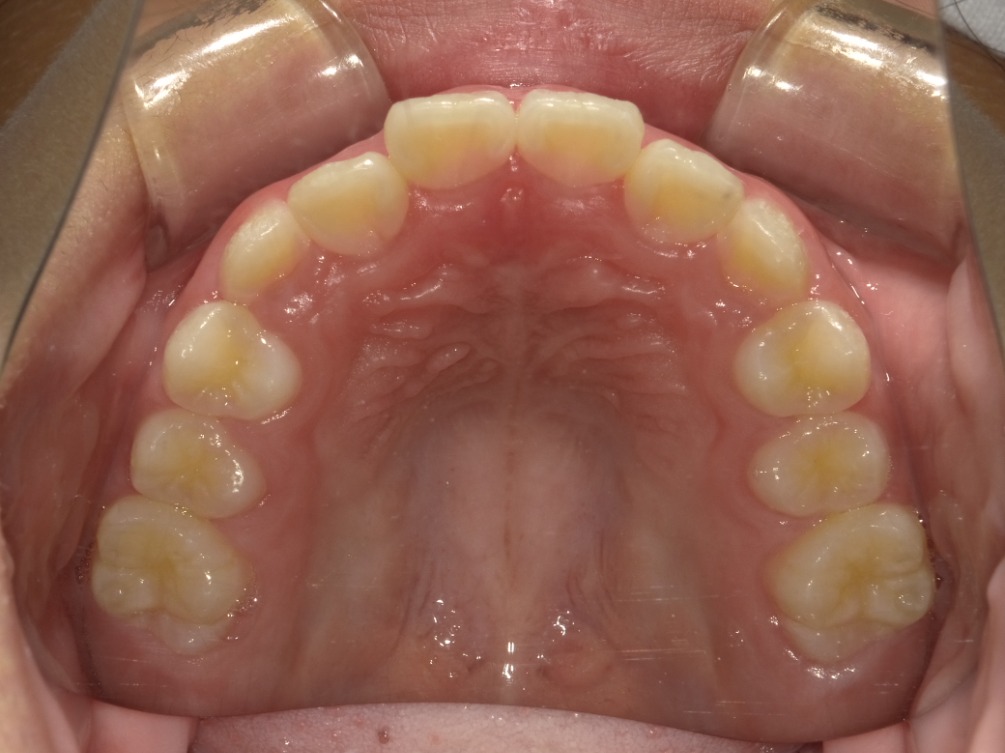

BEFORE

上顎

| 治療内容 | インビザライン・ファースト |

| 治療詳細 | 叢生や交叉咬合を整えるために、歯の表面にアタッチメント(白い突起)をつけました。 |

| 主訴 | 歯のがたつき 一部分だけかみ合わせが反対 |